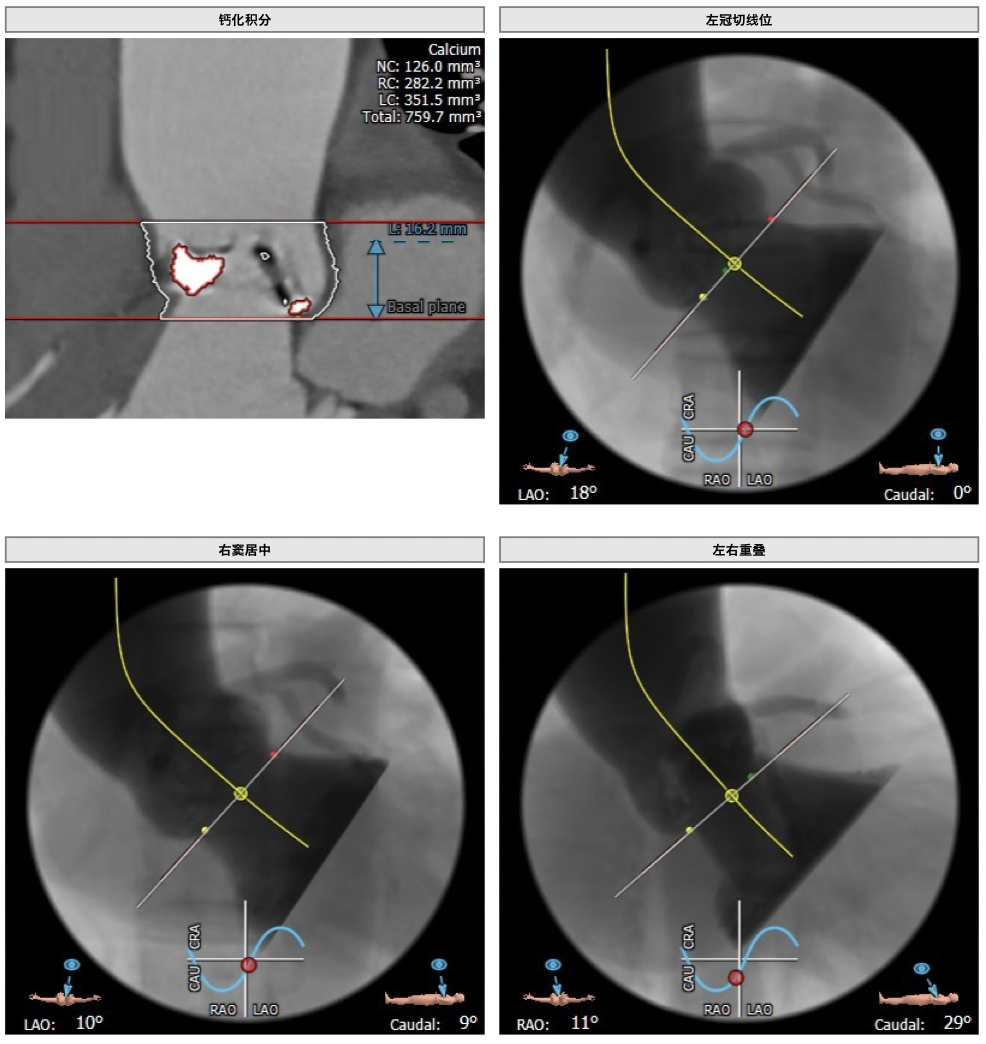

主动脉CT

图片

手术策略

难点分析:

*功能型二叶瓣,瓣叶增厚,重度钙化,瓣环及左室流出道层面仍可见钙化,左右可见钙化融合,瓣膜释放后发生瓣周漏的风险较高,瓣膜释放后容易移位。

*左右股动脉较细,直径小于6mm, 双侧髂动脉-股动脉走形迂曲,可见明显钙化,术中操作需谨慎轻柔,注意血管并发症的发生。

*左室腔较大,术中需注意液体管理。

制定策略:

经分析研判,拟从右侧股动脉穿刺入路,使用22mm球囊预扩,选用L26号的VenusA-Valve瓣膜,采用VenusA-Plus可回收输送系统进一步确保手术安全,瓣膜释放后结合造影和超声情况,决定是否后扩。